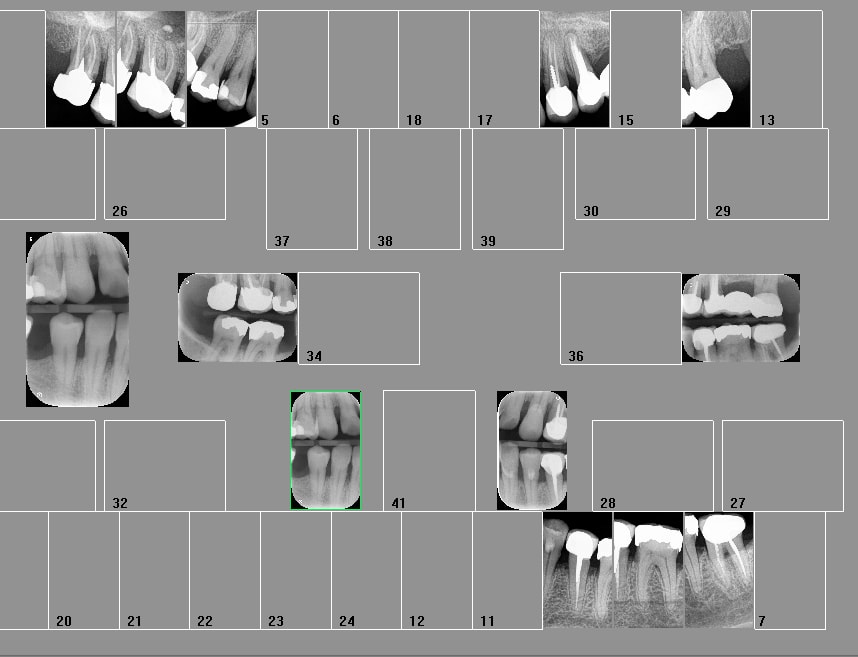

Capture d écran 2017 12 11 09.04 - Eugenol

Sur un film 3+ je vois toutes les couronnes de la 7 a la 3... si je fais bite wing gauche et droit ca fait 20 couronnes, je peux compter combien de secteurs ?

T'es con d'utiliser des films taille 3 surtout avec des CDC de bonne composition. ca fait que 2 secteurs ou 4. Alors que 4 clichés ca fait 4 secteurs....ou 8. Les rétro alvéolaires sont offertes. -)

Capture d écran 2017 12 11 09.50 - Eugenol

Le problème vois tu avec ces films étendus c'est que moins tu as de clichés moins tu as de dents au centre d'un cliché et moins tu as de secteurs. -)))

Capture d écran 2017 12 11 14.35 - Eugenol

Capture d écran 2017 12 11 19.44 - Eugenol